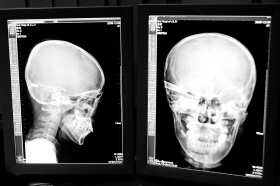

在接受x光檢查的小沖

“還是先做個(gè)X光透視,看一下箭桿到底有多深!毖劭漆t(yī)生緊急趕到CT室查看,和放射科的幾位醫(yī)生共同研究后,決定先讓小沖做X光透視。

“如果再用點(diǎn)力,就從后腦穿出來了!”由于小沖無法移動(dòng),醫(yī)生拿來移動(dòng)插座,將透視的光板放在小沖的移動(dòng)病床上,透視后讓在場(chǎng)的醫(yī)生都吃了一驚:箭桿直接穿過了大腦和小腦,箭尖兒直抵后顱骨,足足有10余厘米。